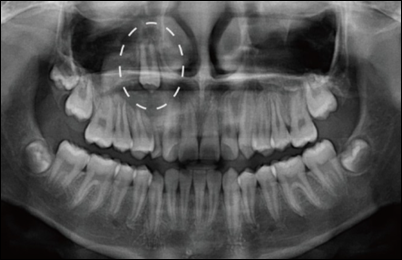

맹출 장애는 특별한 임상적 증상이 없으므로 조기 발견하기가 어렵습니다. 따라서 방사선 검사를 포함한 정기적으로 치과 검진을 받는 것이 중요합니다.

치아 맹출은 사람이 성장함에 따라, 오랜 시간에 걸쳐서 턱뼈 내에서부터 먼 거리를 이동하는 과정입니다. 맹출 장애 주원인으로는 맹출 경로 이상과 과잉치와 같은 맹출 경로상의 국소적 방해입니다.

치배의 위치가 정상 맹출 경로와 전혀 다른 방향으로 바뀌어 있는 경우에 맹출 지연 혹은 매복이 흔히 발생합니다. 또는 치아가 구강 내로 맹출 할 공간이 부족한 경우에도 맹출 장애가 발생할 수 있습니다. 맹출 중인 치아의 맹출 경로상에 과잉치, 치아종, 반흔 조직, 유착된 유치와 같은 장애물이 있으며 치아의 맹출이 더 이루어지지 못하고 그 위치에서 정지하게 됩니다.

방사선 검사나 임상 검사 등을 통해 국소적인 원인이 파악된 경우에는 원인을 제거하는 치료를 해야 합니다. 과잉치, 치아종, 낭종, 맹출 시기가 지난 유치와 같은 치배 주변의 국소적인 원인은 수술을 통해 원인 제거합니다. 국소적인 원인이 없는 경우에 맹출 지연이 나타나는 경우가 있을 경우 전신적 혹은 유전적 원인을 의심해봐야 합니다.